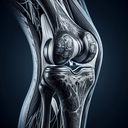

МРТ колінного суглобу

Магнітно-резонансна томографія (МРТ) колінного суглобу — це неінвазивний діагностичний метод, що дозволяє отримати деталізоване зображення структур коліна, включно з кістками, хрящами, зв'язками, сухожиллями та м'язами. **Основні переваги МРТ колінного суглобу:** 1. **Висока точність**: Дозволяє виявляти навіть незначні пошкодження або зміни в тканинах...